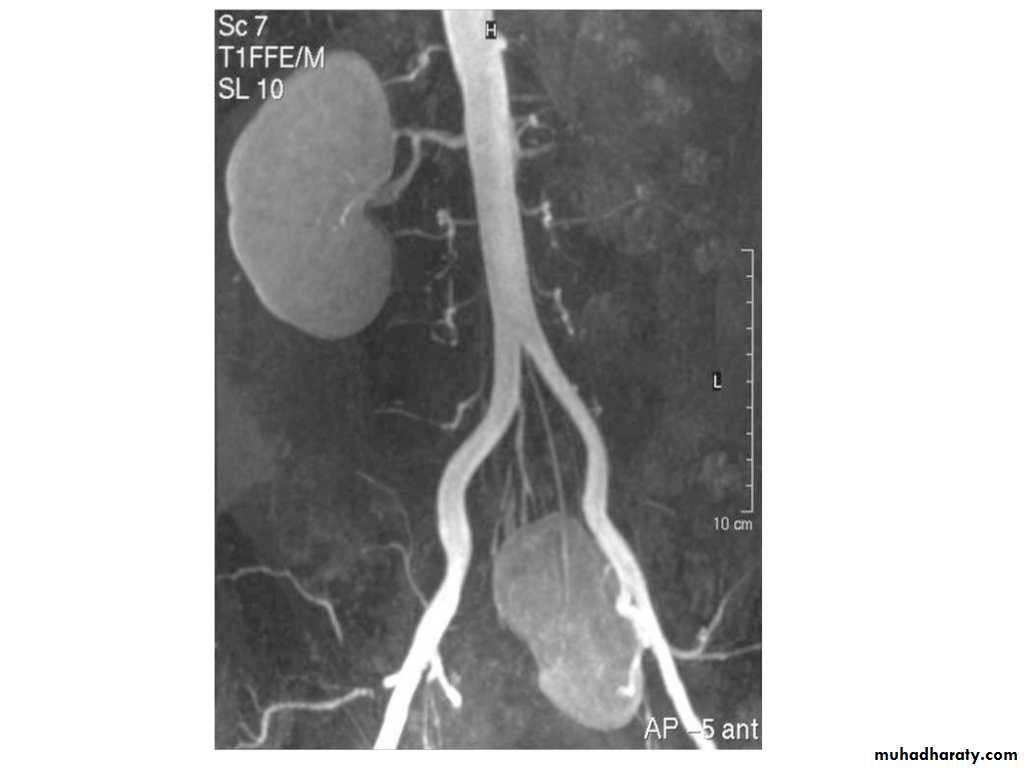

IVU shows

1. The kidneys at low position .2.Close to the spine with long axis parallel to the spine

3. Malrotation manifested by medially directed calyces.

4- The renal pelvis and ureters are anterior and lateral in position.

5- Hydronephrosis and calculi highly associated.